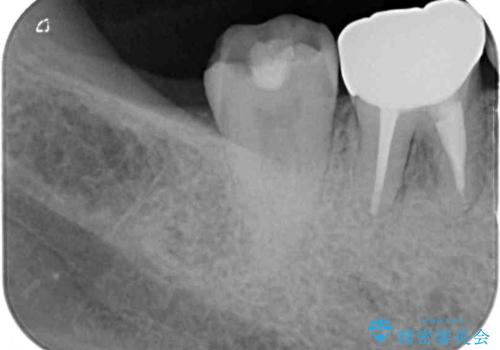

レントゲン写真より、根尖部に病変があったことから、根管治療を行い、症状消失後に補綴治療を行うこととしました。

補綴後6か月経過しレントゲンを撮影したところ、根尖周辺の病変が消失していることが確認できました。